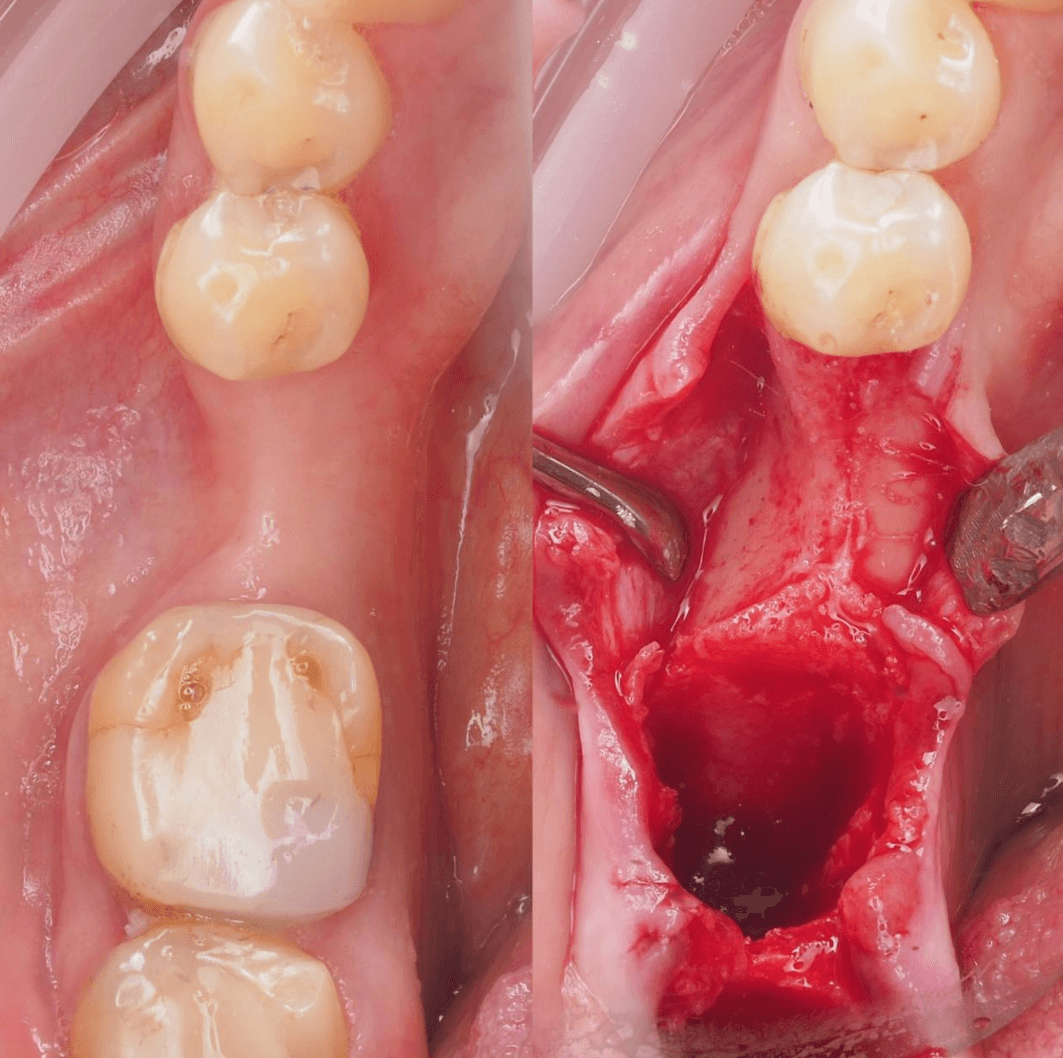

В область отсутствующей шестерки был установлен AnyOne Onestage Tussue Level, а в лунку моляра – широкий AnyRidge + мультиюнит с высотой десны 2,5 мм. Далее пластика мягких тканей.